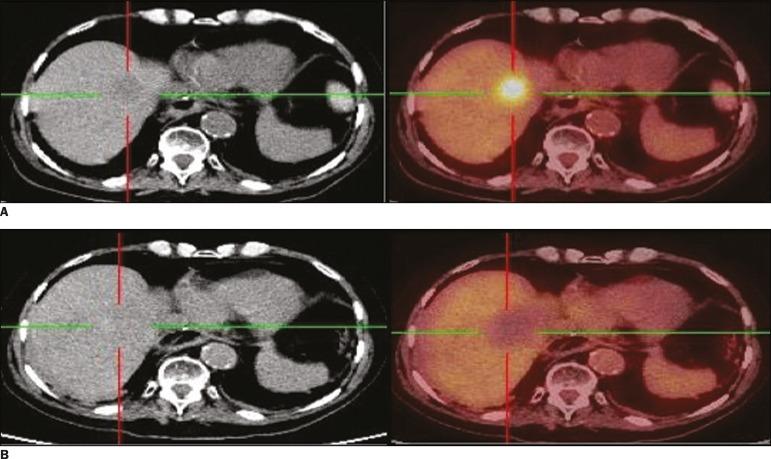

This was a retrospective study of 20 patients (13 males, 7 females; mean age, 65.8 ± 12.1 years) submitted to percutaneous ablation of metastases. All of the lesions treated had shown focal uptake on a F-FDG PET/CT scan obtained at baseline. The primary tumors were mainly colorectal cancer (in 45%) or lung cancer (in 40%). F-FDG PET/CT was performed to identify any residual viable tumor cells. The treatment was considered a success (no viable tumor cells present) if no uptake of F-FDG was noted on the F-FDG PET/CT scan.

Twenty-six lesions were submitted to percutaneous ablation with either cryoablation (n = 7) or radiofrequency ablation (n = 19). The mean lesion diameter was 2.52 ± 1.49 cm. For the detection of viable tumor cells, F-FDG PET/CT had a sensitivity, specificity, accuracy, positive predictive value, and negative predictive value of 66.7%, 95%, 88.5%, 80%, and 90.5%, respectively. There was a significant correlation between the F-FDG PET/CT findings and the results of the follow-up studies (kappa = 0.66; < 0.01).

材料与方法

这是一项对20例接受经皮转移灶消融术患者(13例男性,7例女性;平均年龄65.8±12.1岁)的回顾性研究。所有接受治疗的病灶在基线时的F-FDG PET/CT扫描中均显示局灶性摄取。原发肿瘤主要为结直肠癌(45%)或肺癌(40%)。进行F-FDG PET/CT以识别任何残留的存活肿瘤细胞。如果在F-FDG PET/CT扫描中未发现F-FDG摄取,则认为治疗成功(无存活肿瘤细胞)。

结果

26个病灶接受了冷冻消融(n = 7)或射频消融(n = 19)的经皮消融。病灶平均直径为2.52±1.49 cm。对于存活肿瘤细胞的检测,F-FDG PET/CT的敏感性、特异性、准确性、阳性预测值和阴性预测值分别为66.7%、95%、88.5%、80%和90.5%。F-FDG PET/CT结果与随访研究结果之间存在显著相关性(kappa = 0.66;P < 0.01)。